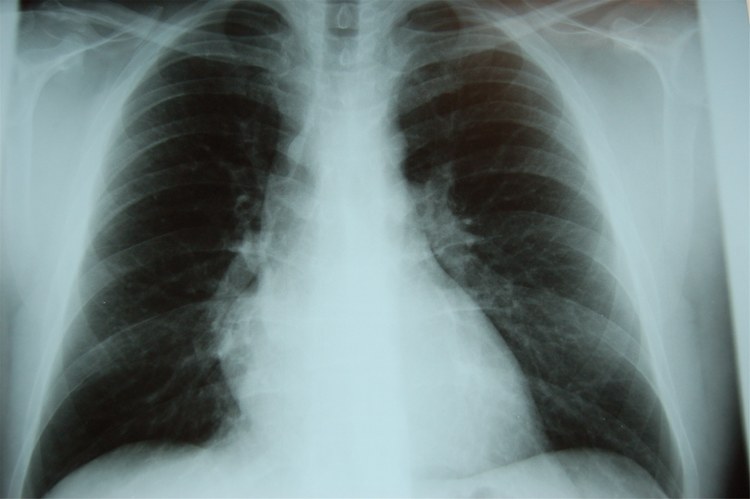

这样的场景让曾经做肺癌筛查工作的志愿者刘韬很有感触。刘韬告诉39深呼吸,曾经,他们的筛查项目进入福建宁德市古田县后,虽然从1000多个人中筛出来了几十多例高危肺结节患者,但最后真正来复查的人,一只手都能数得过来。“医生坚持打了很久的电话,这些人也不愿意过来复查确诊,他们觉得晦气。”

发现肺结节后最重要的一件事是排除肺癌。/ quanjing